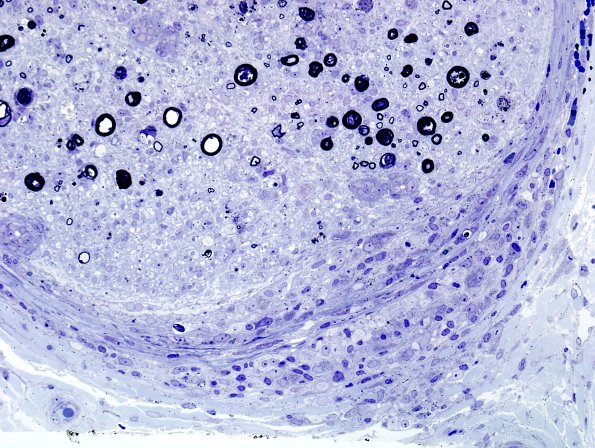

3B6B Sarcoid (Case 3) Plastic 25

A focus of perineurial extension is accompanied by endoneurial small granulomas. (Plastic sections)